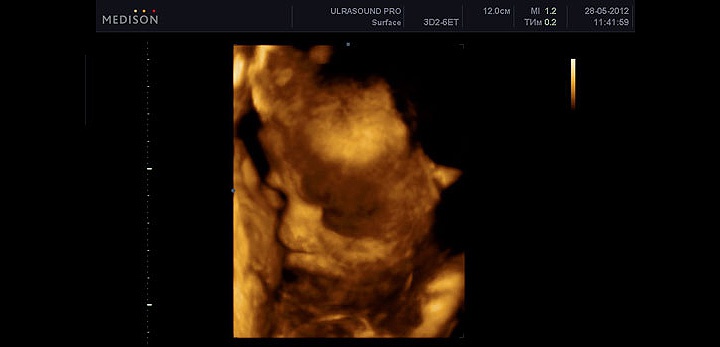

УЗИ на 35 неделе беременности

На 35 неделе УЗИ рекомендуется для оценки состояния плода, его положения и предлежания, а также состояния плаценты и количества околоплодных вод.

На этом сроке вес ребенка составляет около 2400 г, и он продолжает активно набирать вес — от 220 до 350 г в неделю.

Фетометрия (размеры плода) при УЗИ на 35 неделе беременности в норме

- БПР (бипариетальный размер) 81–95 мм.

- ЛЗ (лобно-затылочный размер) 103–121 мм.

- ОГ (окружность головки плода) 299–345 мм.

- ОЖ (окружность живота плода) 285–345 мм.

Нормальные размеры длинных костей при УЗИ на 35 неделе беременности:

- Бедренная кость 62–72 мм.

- Плечевая кость 55–65 мм.

- Кости предплечья 48–56 мм.

- Кости голени 55–63 мм.

УЗИ позволяет оценить активность малыша, его сердцебиение, состояние матки, плаценты и околоплодных вод. На 35 неделе нормой является вторая степень зрелости плаценты, увеличение этого показателя может означать уменьшение ресурсов для малыша.